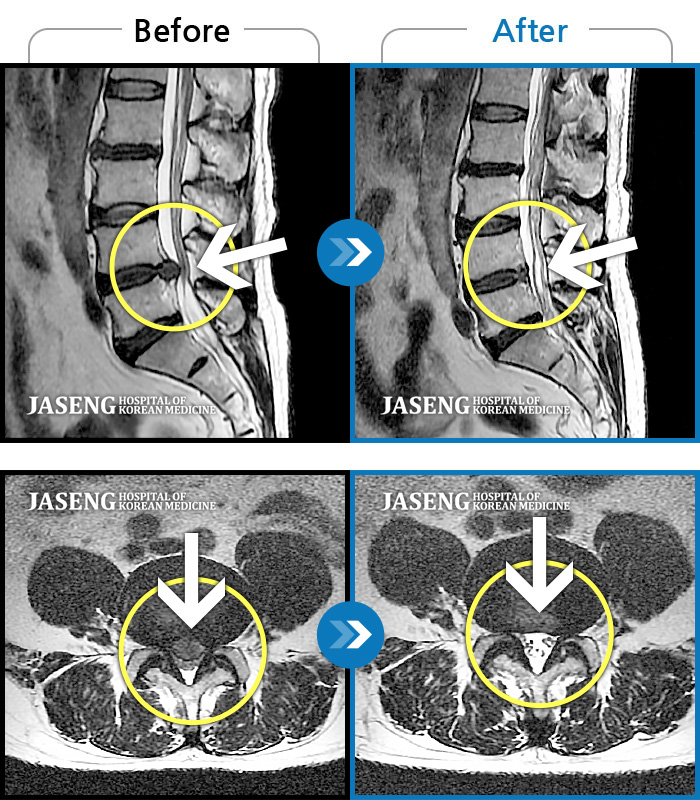

[뱸] 19.11.28~25.05.06